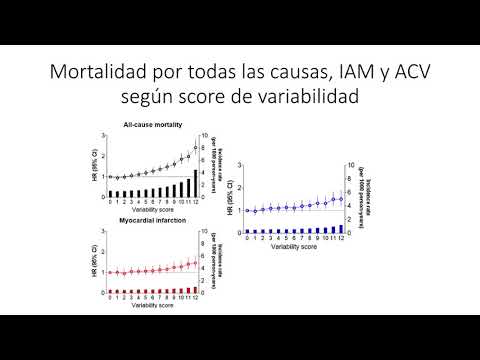

Asociación entre variabilidad de presión, glucemia, colesterol e índice de masa corporal con mortalidad y resultados cardiovasculares en la población general. Dr. Alejandro Kim. Residencia de Cardiología. Hospital C. Argerich. Buenos Aires